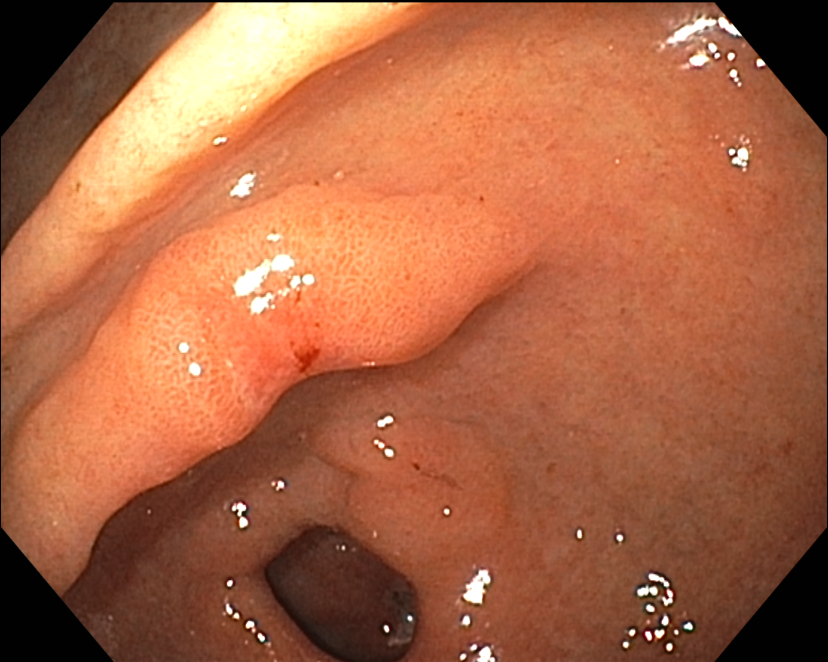

Duodenal ulcer, CLOtest : positive, biopsy proven H. pylori (+++)

PPI 치료 후 위내시경과 CLOtest : negative